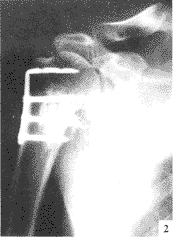

自制L形钢板内固定治疗肱骨外科颈骨折

肱骨骨折;L形钢板;骨折固定术

【摘要】 目的

介绍自制L形钢板治疗肱骨外科颈骨折的疗效。

方法

应用自制L形钢板治疗肱骨外科颈骨折16例 ......